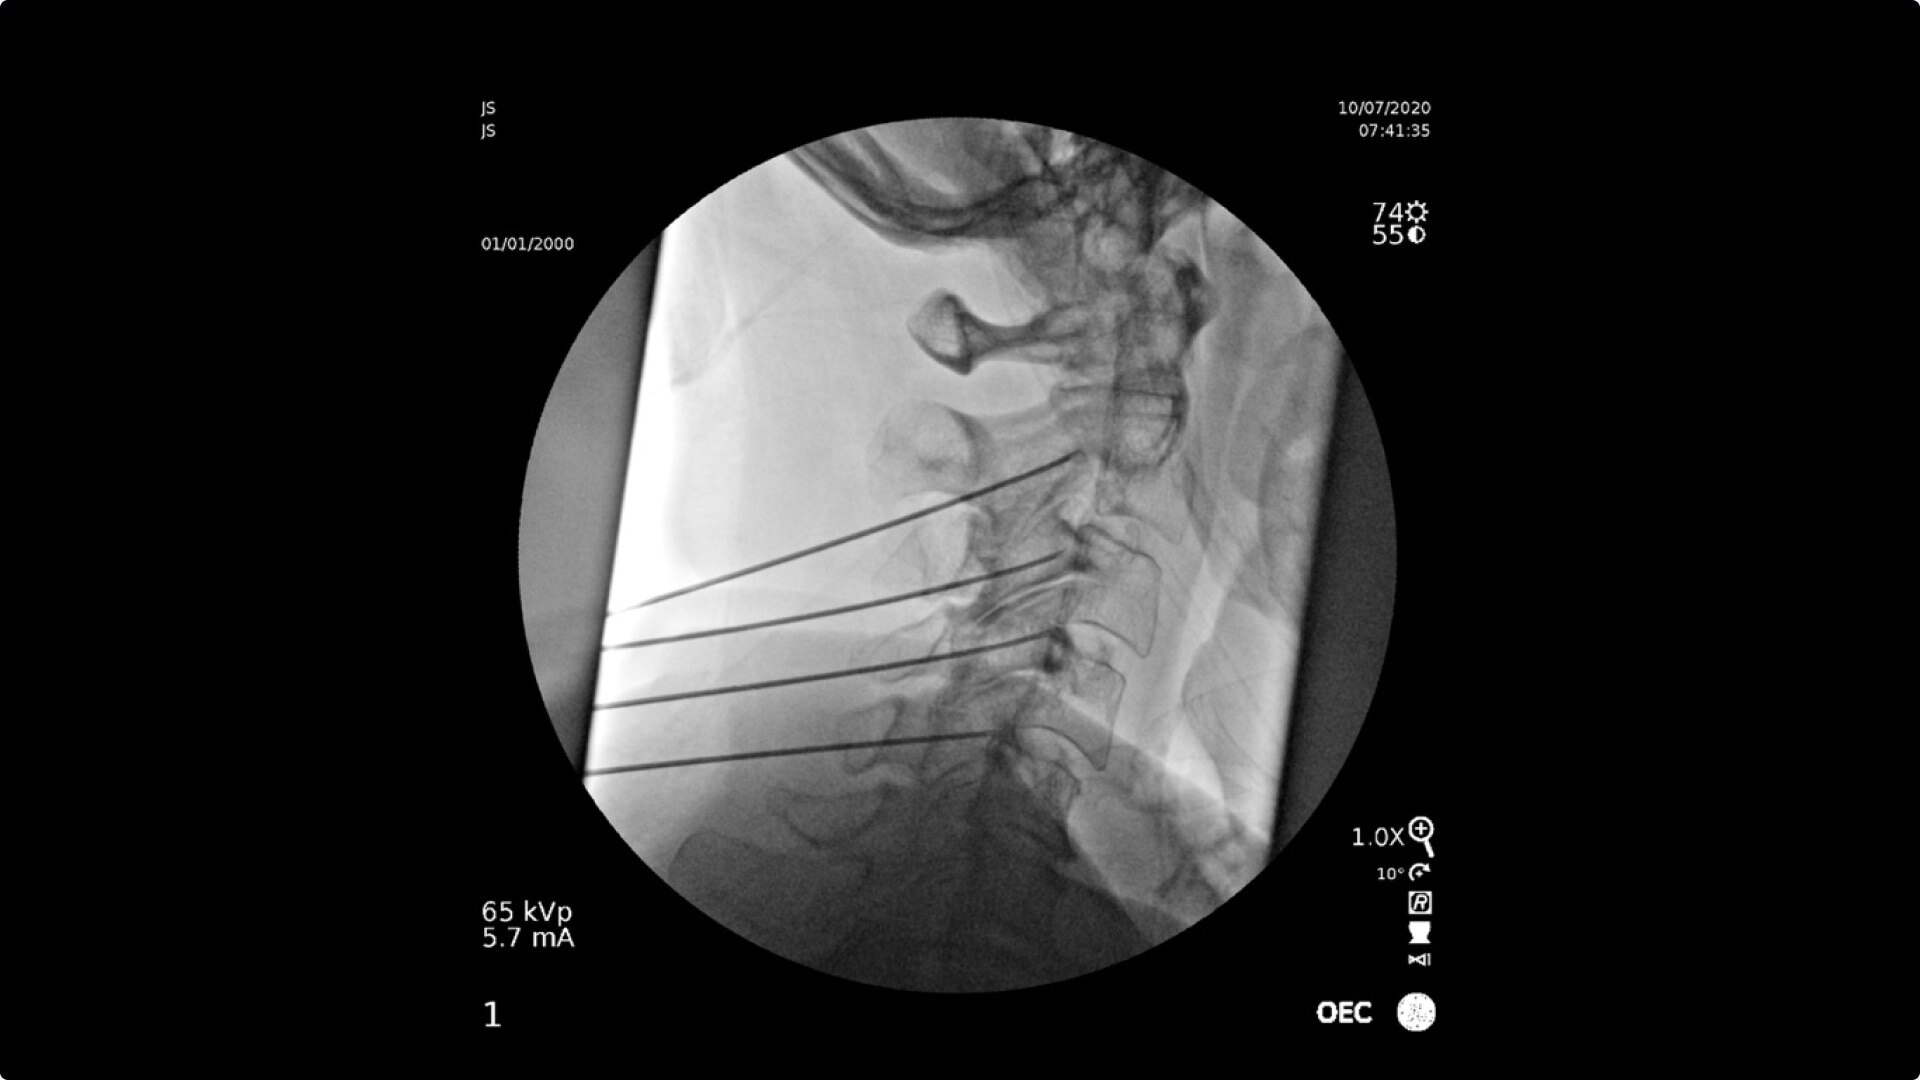

C-arms for Pain Management

Consistently experience amazing image quality, precision, and efficiency during simple to complex pain management procedures with OEC C-arms.

Achieve precision and efficiency while experiencing the image quality needed during simple to complex pain management procedures with OEC C-arms.

Pain management imaging you need

Pain Management procedures require powerful imaging systems.

OEC C-arms perform imaging in a variety of procedures such as:

• Cervical spine pain management